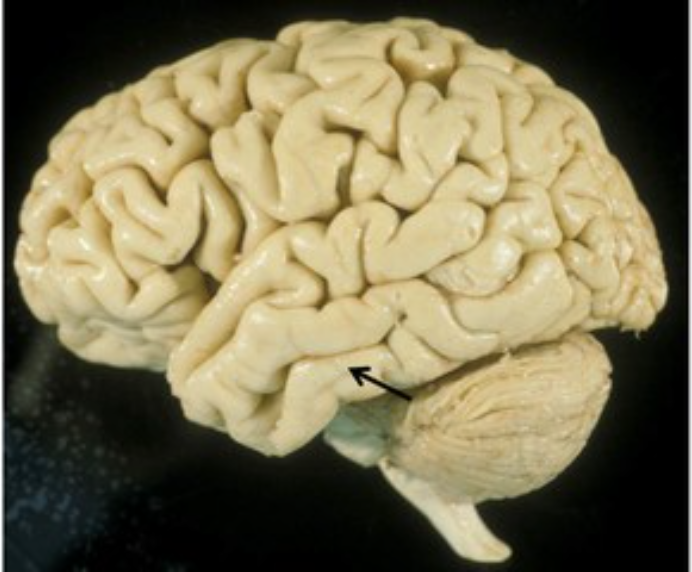

Identify

temporal lobe